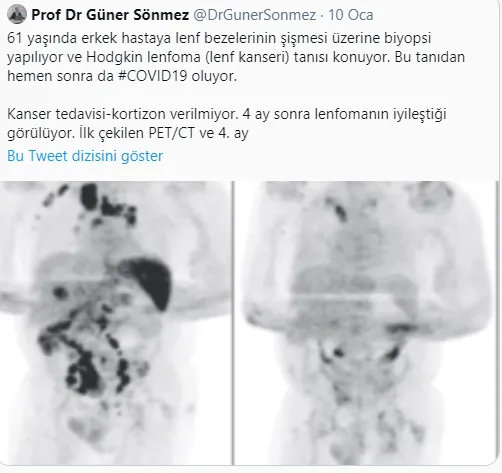

Sönmez, "61 yaşında erkek hastaya lenf bezelerinin şişmesi üzerine biyopsi yapılıyor ve Hodgkin lenfoma (lenf kanseri) tanısı konuyor. Bu tanıdan hemen sonra da #COVID19 oluyor. Kanser tedavisi-kortizon verilmiyor. 4 ay sonra lenfomanın iyileştiği görülüyor. İlk çekilen PET/CT ve 4. ay" dedi.